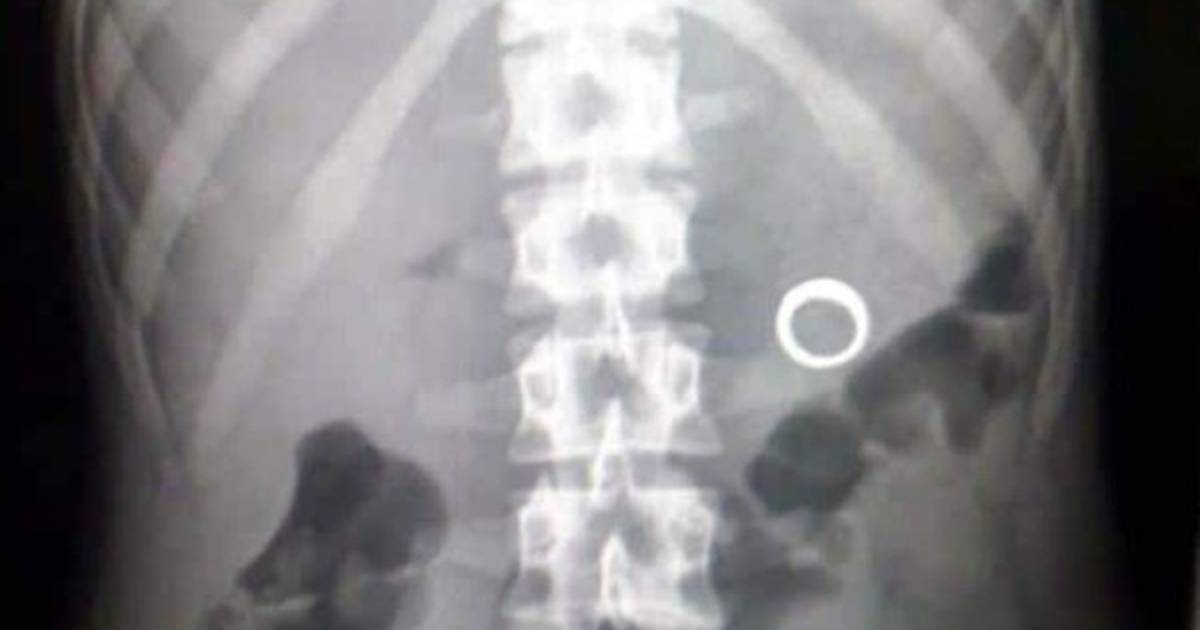

'En una radiografía (que se le tomó) salen los elementos dentro del abdomen', apuntó. La mujer, en tanto, sufrió 'laceraciones' en las orejas.

Los aretes serán usados como prueba contra el delincuente.